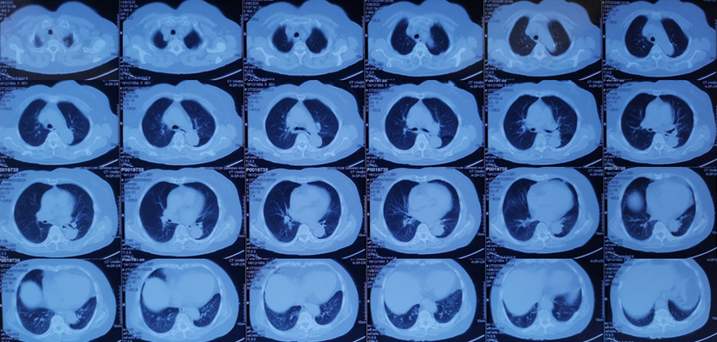

复查全腹部CT考虑不完全性肠梗阻及双肺感染,结合患者病史,考虑“外源性脂质性肺炎”可能性大。予以哌拉西林他唑巴坦抗感染,地塞米松抗炎,中药辅助治疗等;患者于8月20日左右出现发热,最高体温39.0℃,咳嗽咳痰症状较前加重,且伴有明显气促,无畏寒寒战,经治疗后仍有气促不适,为求进一步诊治,遂至我院门诊就诊,以“双肺病变查因”收住我科。起病以来,患者精神差,睡眠可,食欲减退,大便少,小便正常,体重未测。2020年8月13日于当地医院确诊为“不完全性肠梗阻、右肾囊肿”。余既往史无特殊。配偶2019年因肺结核去世。个人史、月经史、婚育史、家族史等均无特殊。体温36.5℃,脉搏82次/min,呼吸30次/min,血压100/57 mmHg。APACHE Ⅱ评分11分,SOFA评分2分,NRS-2002营养风险评分4分。急性面容,神清,精神较差,全身皮肤黏膜未见黄染,全身浅表淋巴结未触及肿大。胸廓无畸形,双侧呼吸动度对称,语颤无增强,双肺叩诊清音,双肺呼吸音粗,双肺可闻及干啰音,未闻及胸膜摩擦音。心率82次/min,律齐,各瓣膜听诊区未闻及病理性杂音。腹软,全腹无压痛及反跳痛,未触及腹部包块,肝、脾肋缘下未触及,腹部移动性浊音阴性,双肾区无叩击痛。肠鸣音正常。无杵状指(趾),双下肢不肿。2020年8月31日我院胸部CT示右肺弥漫性实变为主,伴渗出,左下肺亦有少许渗出(图3)。①双肺病变查因:外源性脂质性肺炎?Ⅰ型呼吸衰竭;②不完全性肠梗阻;③低蛋白血症;④低钠血症;⑤右肾囊肿。- 血气分析:pH 7.501,PaCO2 31.7 mmHg,PaO2 48.3 mmHg,Lac 0.9 mmol/L,HCO3- 25.9 mmol/L。